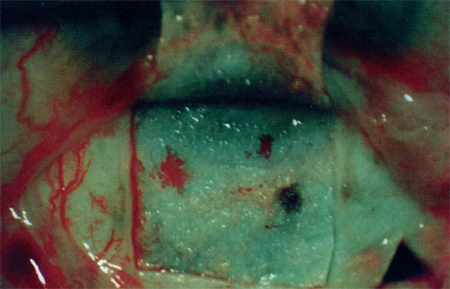

После гемостаза выкраивали глубокий склеральный лоскут с одновременным удалением наружной стенки склерального синуса и части роговичной ткани (до десцеметовой оболочки) кпереди от пограничного кольца Швальбе (на 1,5-2,0 мм). После завершения НГСЭ приступали к проведению меридианальных надрезов глубоких и средних слоев склеры глубиной 0,5-0,6 мм в таком виде, как это показано на рис. 3. Расстояние между меридиальными надрезами - 0,8-1,0 мм, что позволяет долее углублять и расширять их за счет термо- или диатермокоагуляции прилежащих интактных слоев склеры.

Меридиональные надрезы глубоких и средних слоев склеры

Рис. 3 Меридиональные надрезы глубоких и средних слоев склеры